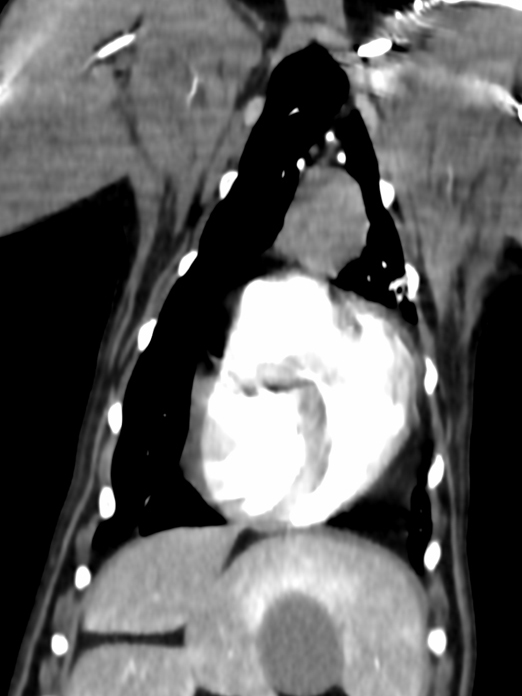

他疾患の手術前検査として実施した胸部レントゲン検査にて、前縦隔部に腫瘤性病変を認めたことから、精査のためCT検査を実施しました。 CT所見より、胸腺腫や異所性甲状腺腫瘍などの腫瘍性疾患が強く疑われたため、胸腔鏡を用いた腫瘤摘出術を行いました。 術前より臨床症状は認められず、全身状態も良好であったため、術後の経過は順調であり、術後2日目に退院となりました。

手術前のCT検査